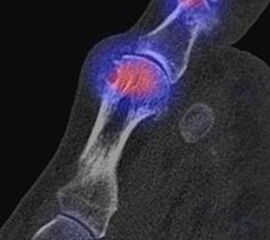

Abbildung 1.6.

Bekannte Gicht mit Polyarthralgien. Am rechten Großzehengrundgelenk lateral in der Grundphalanx entzündliche Erosionen.

Abbildung 1.7.

Gichtarthritis mit Osteolysen und flauen Verkalkungen in den periartikulären Weichteilen/Gelenkkapsel.

Abbildung 1.8.

Abbildung 1.8.a und b: Akute Arthritis bei bekannter Gicht in beiden OSG: links die Früh-/Weichteilphase; rechts die Mineralisations­phase. Deutliche, entzündlich bedingte Mehranreicherungen in der Früh-/Weichteilphase. In der Mineralisation­sphase erkennt man die entzündliche Mitreaktion der subchondralen Gelenkabschnitte.

Zum Lesen der Bildbeschreibung und zur Vollansicht bitte das Bild anklicken. Bild: H. C. Rischke

Abbildung 1.8.c - e: Akute Arthritis in beiden OSG, rechts > links. Im SPECT/CT erkennt man die Mitreaktion der subchondralen Gelenkabschnitte. Die Arthritis ist so akut, dass (noch) keine ossären morphologischen Veränderungen im CT abgrenzbar sind.

Zum Lesen der Bildbeschreibung und zur Vollansicht bitte die Bilder anklicken. Bilder: H. C. Rischke